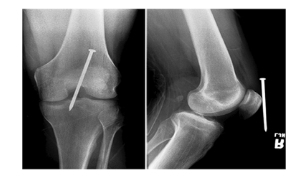

MINIMUM TWO VIEWS/PROJECTIONS

Anatomic structures superimposed ( Placed or laid on top of each other)

Localization of lesions or foreign bodies ( For example the nail near the knee)

Determination of alignment of fractures ( For example: the alignment of the tibia )

1 x-ray done straight on ( PA or AP) → Nail seems deep

1 x-ray 90 degree from that projection for true lateral → Nail adjacent to knee after true lateral

Positioning Rules and Principles

Joints in a prime interest area how many projections?

Three

AP or PA

Lateral

Oblique